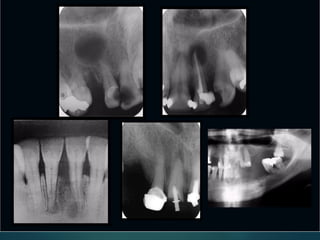

Lesiones

Periapicales

Desde el punto de vista rx

 Línea periodontal apical engrosada

 Granuloma

 Quiste

 Osteítis

 Osteítis condensante

Granuloma

 Area radiolúcida

 Redonda u oval

 Límites netos

 Generalmente no

corticalizado

 Tamaño variable (no

mayor a 1 cm)

 Signos de infección

pulpar

Quiste

 Redonda u oval unilocular

 Bordes bien definidos

 Habitualmente

corticalizada

 Tamaño mayor a 1 cm

 Pueden expandirse a seno

maxilar

 Pueden producir rizálisis en

dientes adyacentes

Osteítis

Osteitis

 Límites difusos

 Tamaño variable

 Diente infectado

 Concepto radiográfico

Condensante

 Area radiopaca

 En relación a un diente

infectado